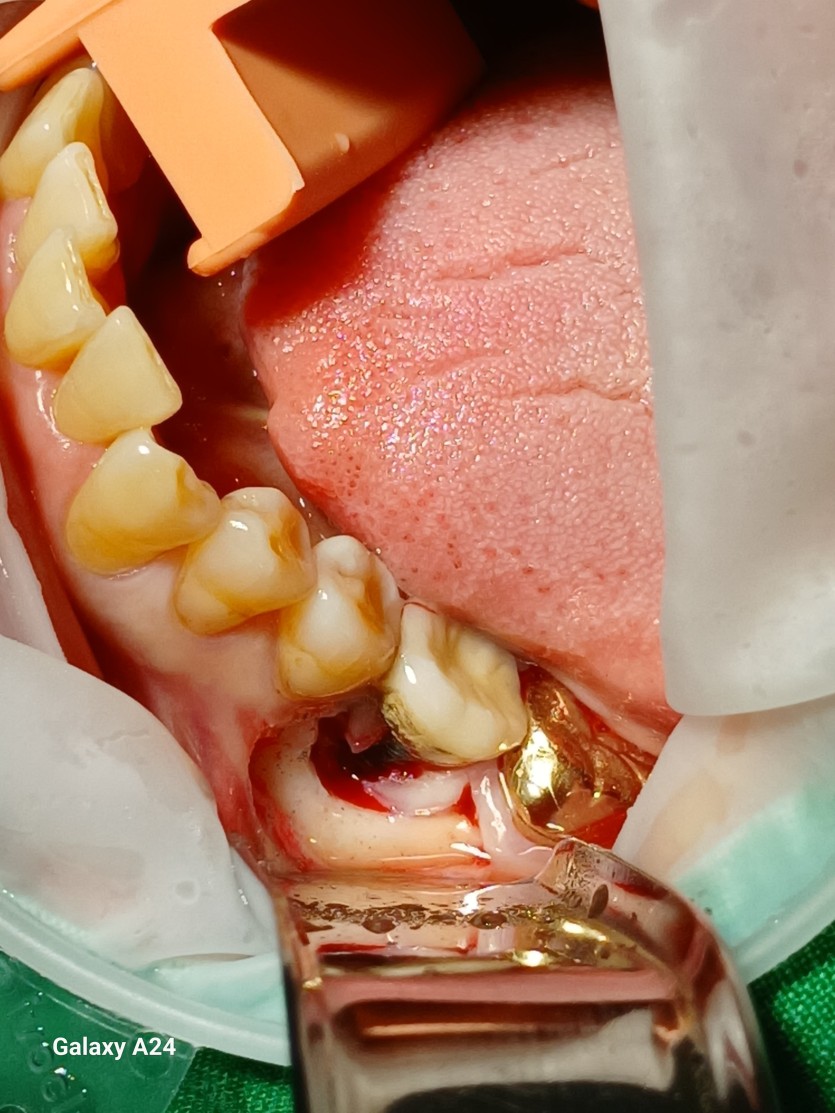

#36 타병원 임플란트 뼈이식 + 재식립